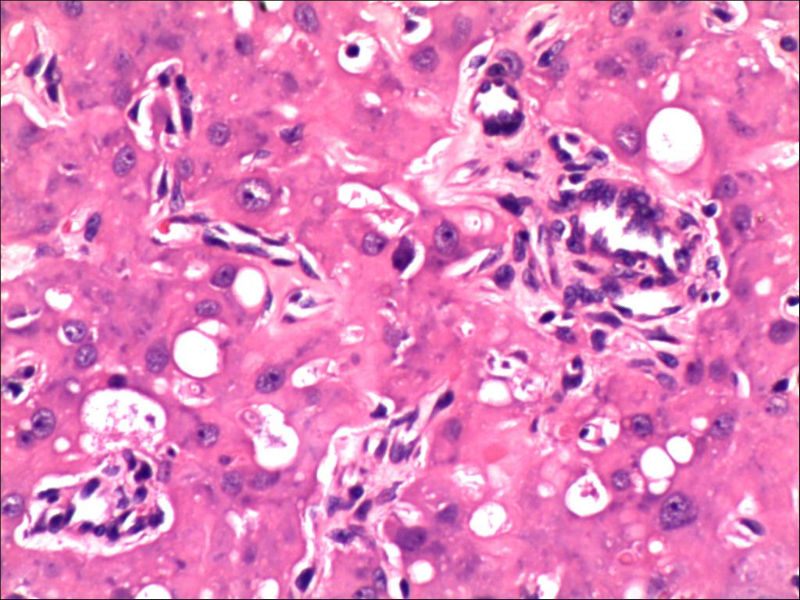

女,27岁,送检右侧卵巢肿物(另外还送检左侧卵巢肿物,大体及镜下显示为畸胎瘤),卵圆形,大小2×1×1cm,似有包膜。卵巢肿物图1

卵巢畸胎瘤中正常卵巢的黄体组织,铺砖样排列,胞浆宽大,较典型。

不好意思,可能是我没说清楚,患者对侧卵巢是畸胎瘤,不是同一侧的,我初步考虑门细胞瘤,图21,22,24,25,26中央的一些细胞是不是很像门细胞

谢谢大家的回答和解疑,忘记一个重要的病史,就是该女性为产妇。但是妊娠黄体瘤与类固醇细胞瘤怎么鉴别呢

那应该是妊娠黄体/黄体瘤,类固醇细胞瘤有嗜酸细胞和组织细胞样细胞两种,此例显然不是。